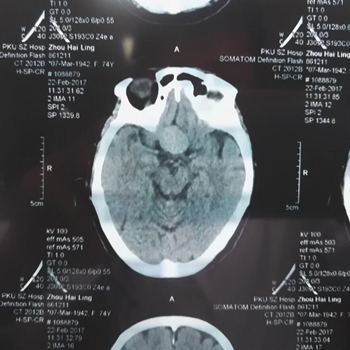

于是邢主任给她做了进一步检查,通过OCT与视野计检查结果,邢宝刚主任判断张奶奶视野缺损的情况应该不是单纯的眼睛问题,极有可能是脑内肿瘤引起的。于是邢宝刚主任建议张奶奶去做脑部CT扫描检查。

没想到,这一查,果然脑部长了一个约21*25mm大小的肿瘤,就是它压迫了视神经,导致视野缺损。“脑子里的肿瘤,这个尺寸已经是很大的了。”